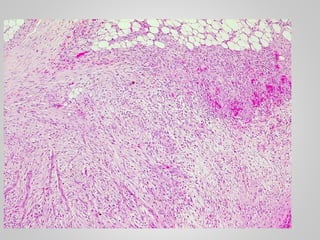

• Gray-white, firm, poorly demarcated

masses

• Varying from 1 to 15 cm in greatest

diameter

• Rubbery and tough

• Marked infiltration of surrounding

muscle, nerve and fat.

• Cytologically bland fibroblasts

arranged in broad sweeping fascicles

amid dense collagen

• Gray-white, firm,poorly demarcated masses • Varying from 1 to 15 cm in greatest diameter • Rubbery and tough • Marked infiltration of surrounding muscle, nerve and fat. • Cytologically bland fibroblasts arranged in broad sweeping fascicles amid dense collagen